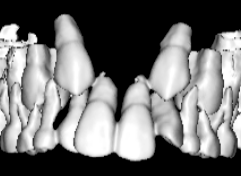

治療開始時

上下顎のギャップはありますが、顔面自体の幅径は良好な値を示していますので、スペース不足は拡大することによって解決できポテンシャルはあると考えられます。

検査時のレントゲン分析では、上下顎の関係は、上顎の劣成長があり下顎前突傾向という値がでておりましたが、前歯ジャンプ後はフェイスマスクの効果もあり、上下顎の関係は正常化しています。

上顎が若干優位になっていますので、今後の下顎の成長のための貯金になっているくらいです。